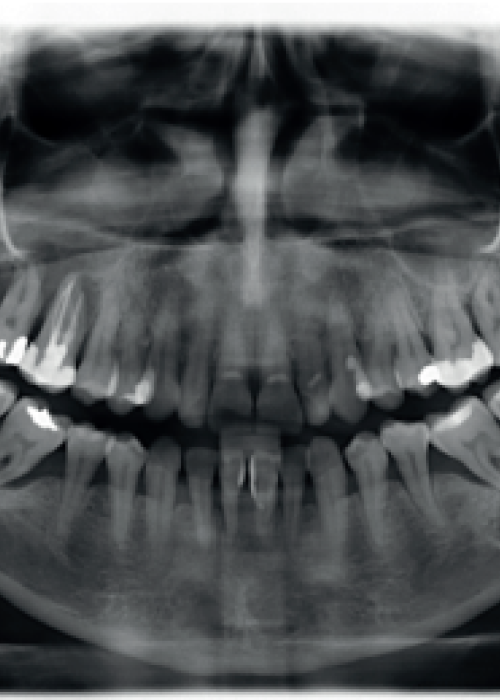

Explantación de implante mal posicionado en sector estético y regeneración posterior con injerto en bloque